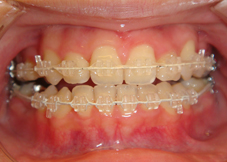

<治療途中>

上下前歯の突出およびでこぼこを改善するために上下小臼歯という歯をそれぞれ2本ずつ(計4本)抜歯しています。前歯の噛み合わせと歯並びがだいぶ改善してきているのが分かります。この後さらに上下の噛み合わせを改善します。

左:初診時、右:治療開始1年11ヶ月

左:初診時、右:治療開始1年11ヶ月(治療途中)